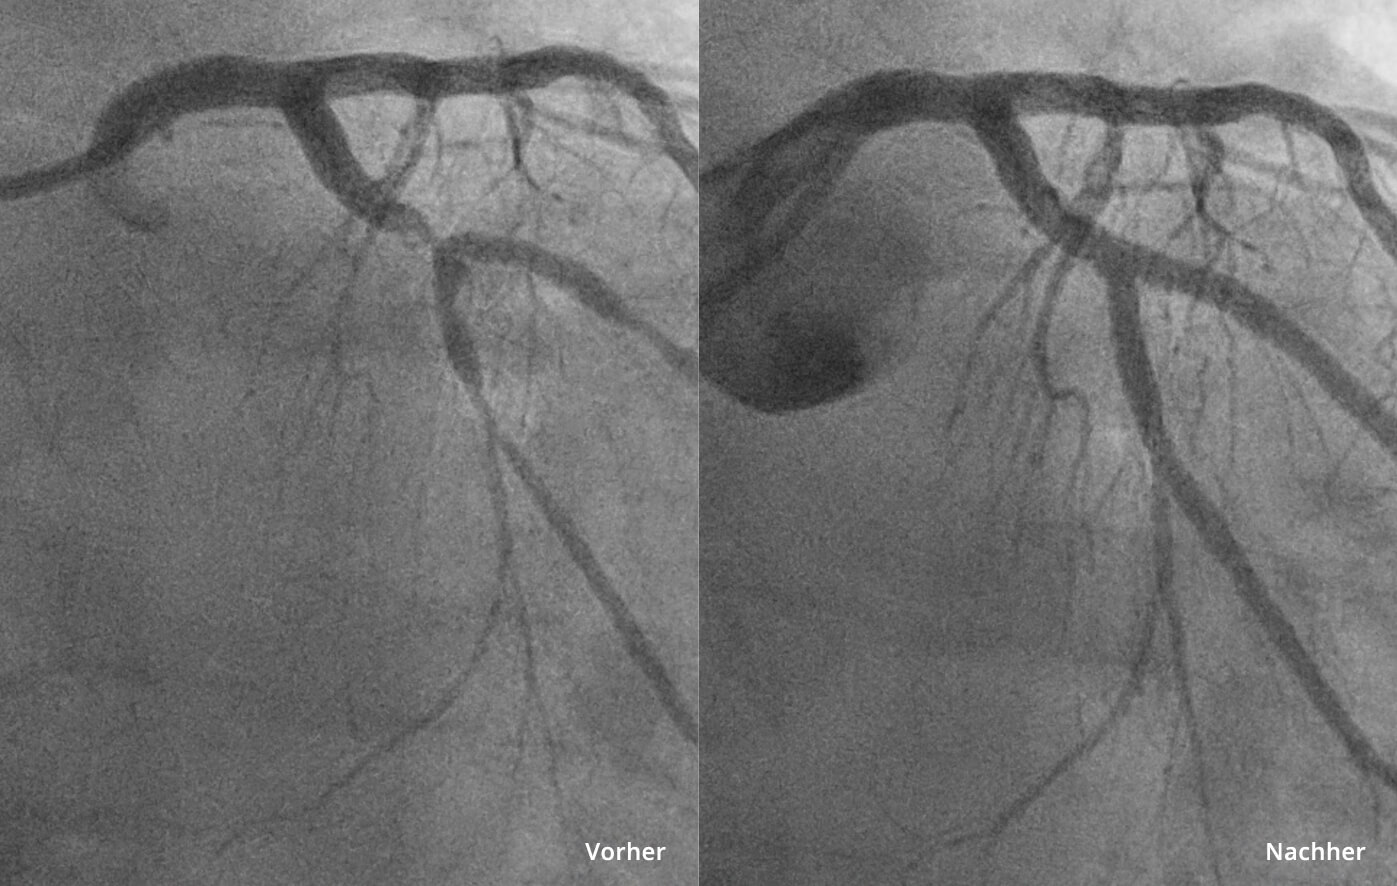

Die besonders wirkungsvolle und gleichzeitig schonende Therapie ist die perkutane Koronarintervention (PCI), auch PTCA genannt. Hierbei wird über einen kleinen Zugang – zumeist über die Handgelenksarterie – ein feiner Katheter zu den betroffenen Gefäßen vorgebracht. Über diesen werden die Herzkranzgefäße mit Hilfe von Kontrastmittel unter Röntgendurchleuchtung dargestellt. An der Engstelle wird ein kleiner Ballon aufgeblasen, der das Gefäß aufdehnt (Ballondilatation). Um sicher zustellen, dass das Gefäß offen bleibt, wird im Anschluss ein Stent (Gefäßstütze) implantiert – eine hauchdünnes Metallgeflecht, die sich dauerhaft in der Arterie verankert und den ungehinderten Blutstrom wiederherstellt.Der Eingriff erfolgt unter örtlicher Betäubung, in manchen Fällen ambulant oder mit kurzem stationärem Aufenthalt (eine Nacht). Wir begleiten Sie während des gesamten Prozesses – von der genauen Diagnostik über die Katheterintervention bis hin zur Nachsorge.